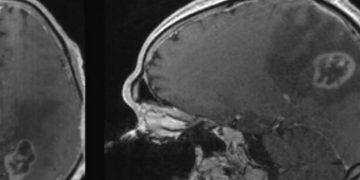

Ученые из Университета Северной Каролины доказали возможность исцеления от онкологических заболеваний при помощи диеты, без применения медикаментов или хирургического вмешательства. Они научились провоцировать ферроптоз — механизм гибели клеток, который связан с содержанием в них железа. Он присущ в первую очередь именно раковым клеткам, таким как глиобластома, смертность от которой достигает 100%, при этом лекарств от нее не существует.